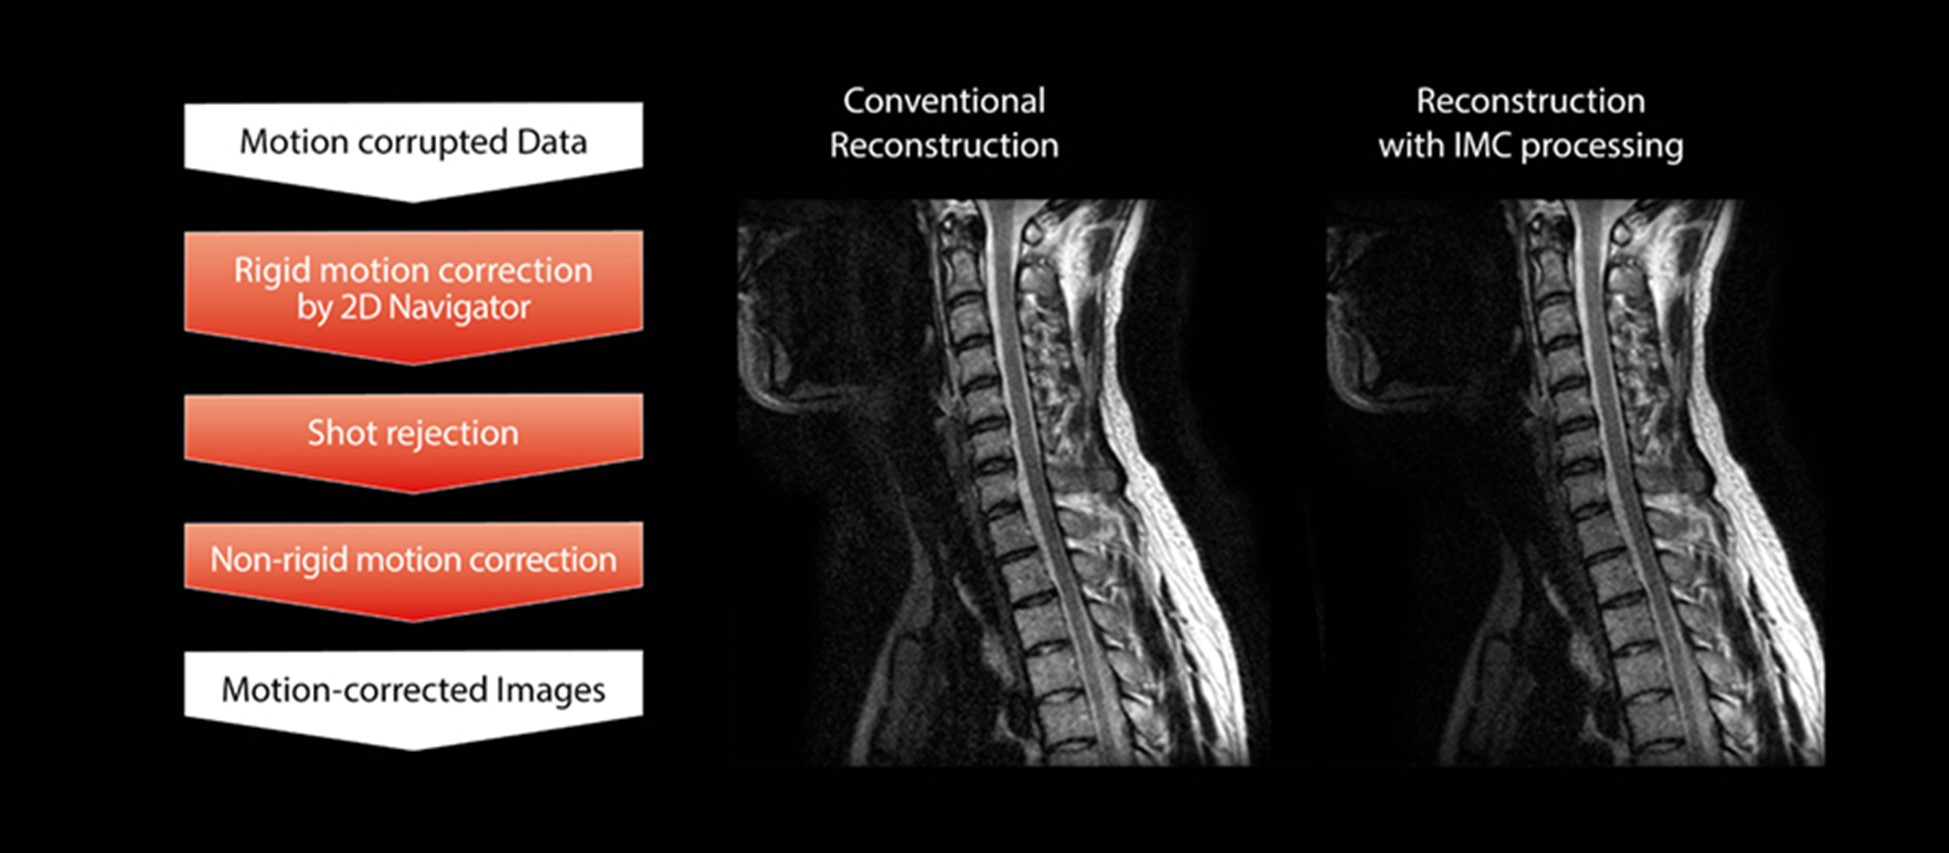

IMC коригує не тільки рухи твердого тіла, а й рухи нетвердого тіла. Цей процес корекції показано на рис. 2.

Рис. 2: Блок-схема обробки реконструкції ітеративної корекції руху для руху нежорсткого тіла (ліворуч) і порівняння зображень із/без IMC (праворуч).

Як показано на рисунку, корекція руху нетвердого тіла спочатку виконується за допомогою 2D навігаційної послідовності. Це відрізняється від описаного раніше методу, який по черзі виконує корекцію твердого тіла та реконструкцію паралельного зображення, однак ціллю для руху, який потрібно виправити, є той самий поступальний і обертальний рух. Потім виконується відхилення неправильних даних, щоб зберегти точність корекції шляхом виключення даних із великими змінами. Потім виконується корекція нежорсткого тіла.

Корекція нежорсткого тіла використовує процес створення синтетичних даних із даних неповної вибірки в k-просторовій області. Одна лінія в напрямку RO розглядається в k-просторі отриманих даних після корекції твердого тіла. Отримані дані порівнюються з синтетичними даними, створеними шляхом оцінки навколишніх даних. Якщо узгодженість погана, на отримані дані, ймовірно, вплинули рухи пацієнта, і вони заміняються синтетичними даними. Таким чином, можна підготувати дані k-простору, зі зменшеним впливом руху в цілому, і, нарешті, отримати реконструйоване зображення, в якому вплив руху на якість зображення зменшений.